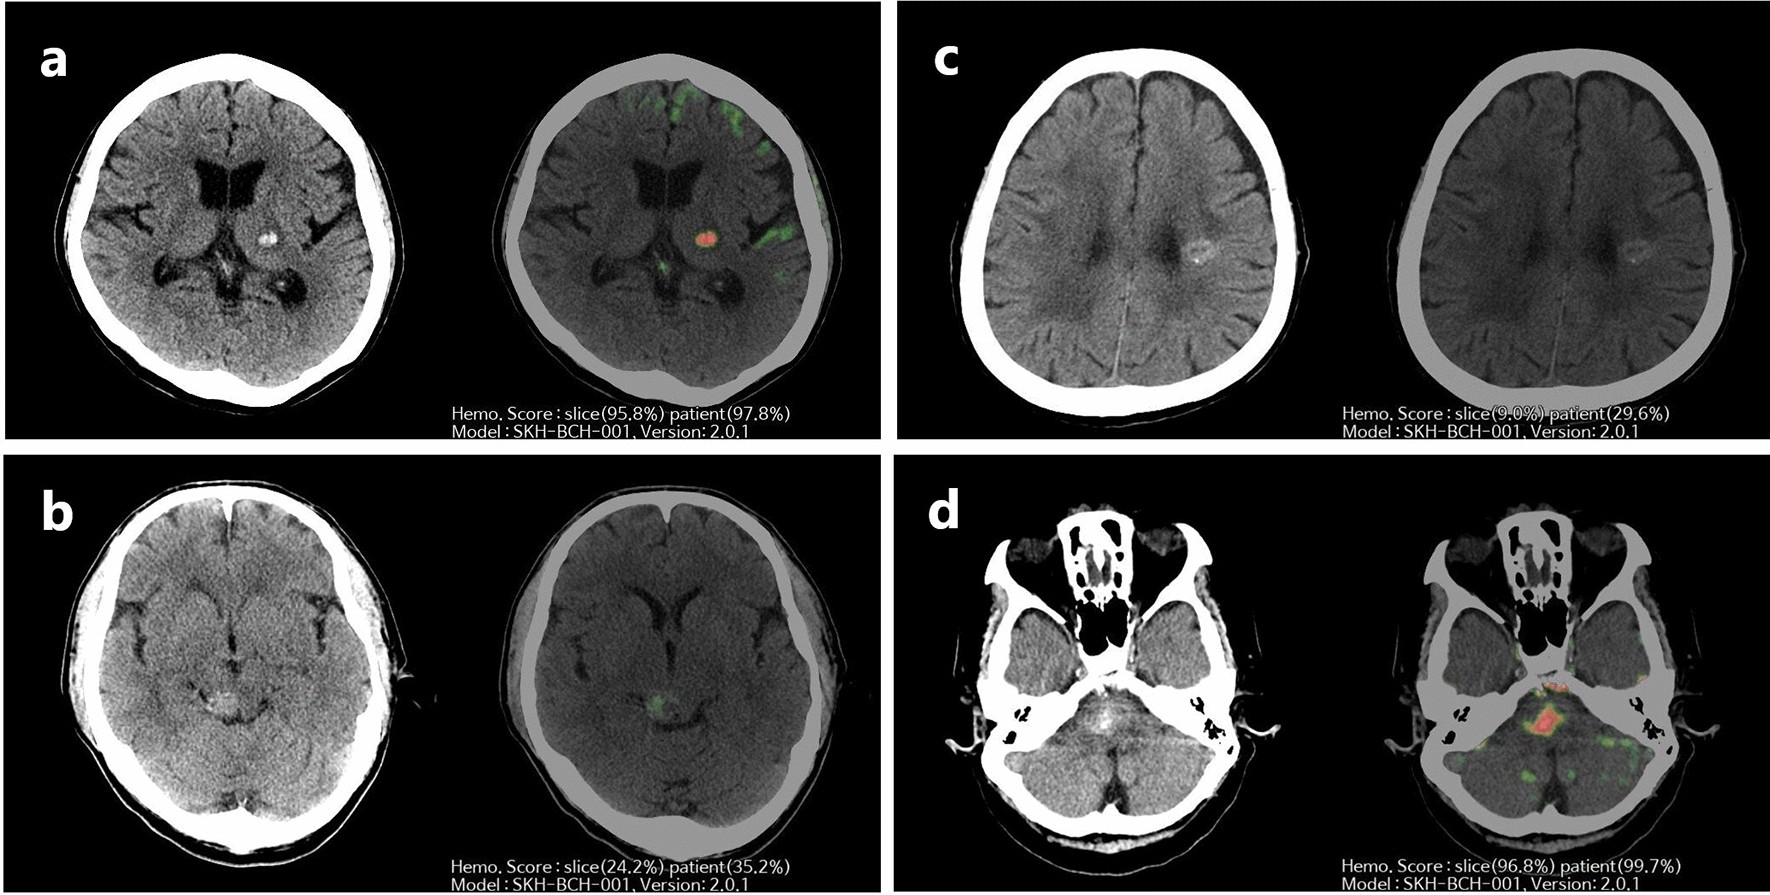

Figure 2

Representative images of the AI algorithm for differentiating CCM and AIH. AI, artificial intelligence; CCM, cerebral cavernous malformation; AIH, acute intraparenchymal hemorrhage; CT, computed tomography. (a) Brain CT shows AIH in the left thalamus. AI-assisted brain CT analysis provided probability scores of hemorrhage in a slicewise (95.8%) and patientwise (97.8%) manner. All six reviewers correctly interpreted the images as AIH for both AI-unassisted and AI-assisted interpretations. (b) Brain CT shows a CCM on the right side of the midbrain. AI-assisted brain CT analysis provided a probability score of hemorrhage in a slicewise (24.2%) and patientwise (35.2%) manner. One radiology resident and one emergency department physician incorrectly interpreted the images as AIH in the AI-unassisted brain CT. However, with the use of AI assistance, all reveiwers correctly diagnosed the images as CCM. (c) Brain CT shows a CCM in the left corona radiata. AI-assisted brain CT analysis generated probability scores of hemorrhage in a slicewise (9.0%) and patientwise (29.6%) manner. All six reviewers accurately identified the images as CCM for both AI-unassisted and AI-assisted interpretations. (d) Brain CT shows AIH in the pons. AI-assisted brain CT analysis generated a probability score of hemorrhage in a slicewise (96.8%) and patientwise (99.7%) manner. All neuroradiologists and emergency department physicians erroneously interpreted the images as CCM in the AI-unassisted brain CT. Nevertheless, with the use of AI assistance, all reviewers accurately diagnosed the images as AIH.